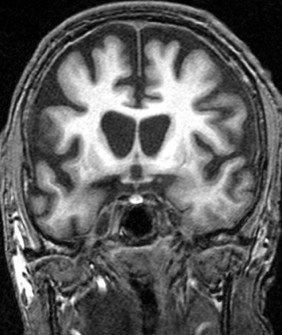

Huntingtons Disease

A progressive neuro-degenerative disease causing uncontrolled physical movements and mental deterioration.